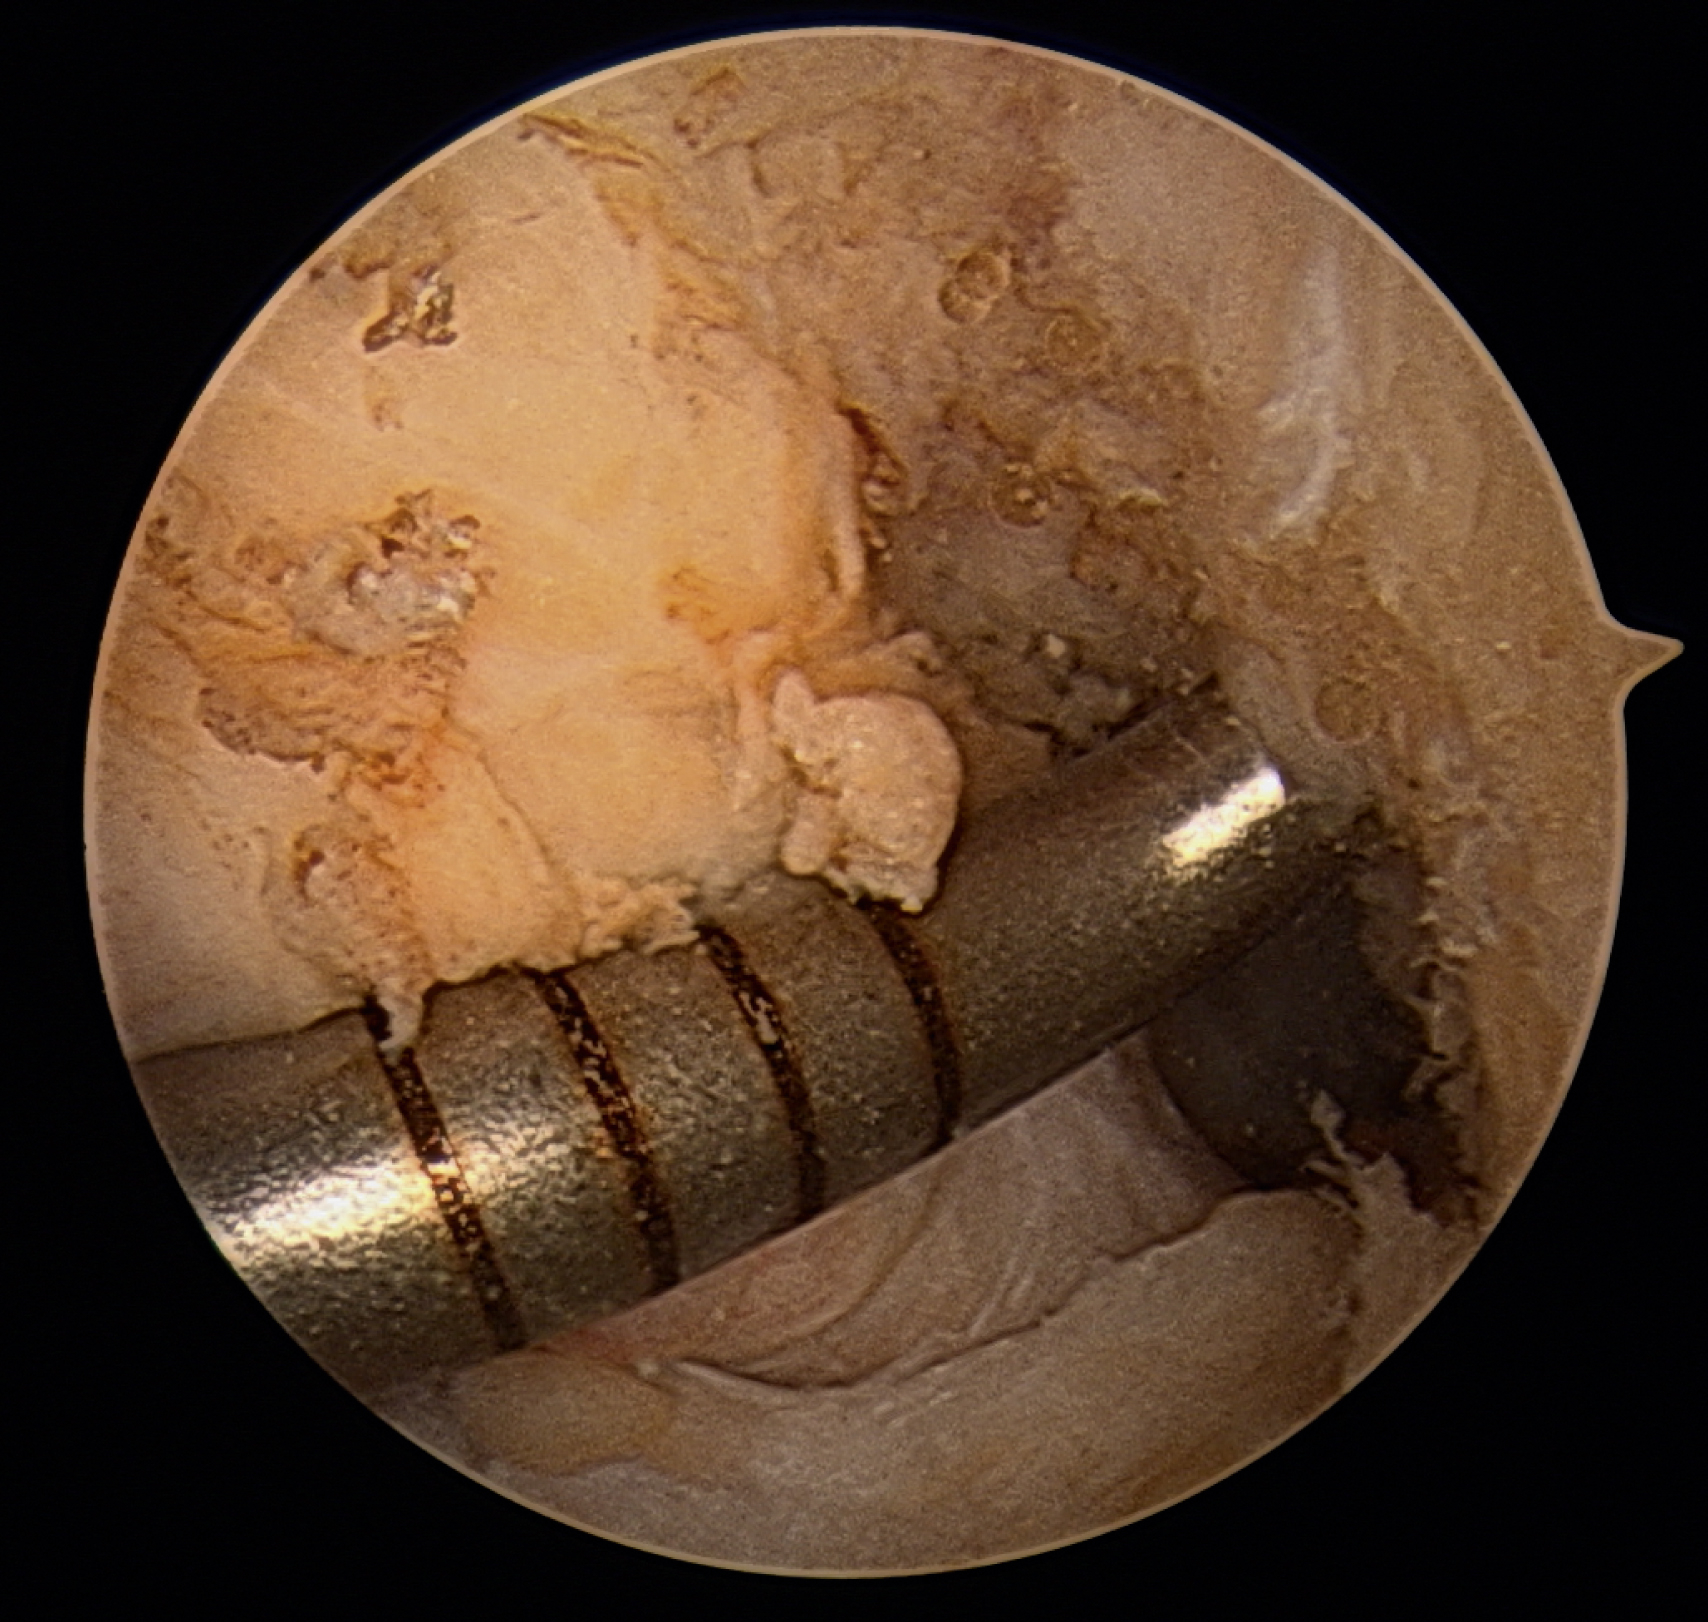

A minimal notchplasty (2 mm) of the lateral wall will facilitate visualization, and a débridement of soft tissue from the lateral wall will also help locate the ACL center. After identifying the point for the femoral tunnel, an awl is used through the medial portal to create a pilot hole for reaming (

). It is helpful to verify the position of the pilot hole by visualization through

the medial portal. The pilot hole should be approximately 8.5 mm (range 8.0–9.5 mm) up the lateral wall and slightly deep to the midpoint between the front and back of the notch (

).